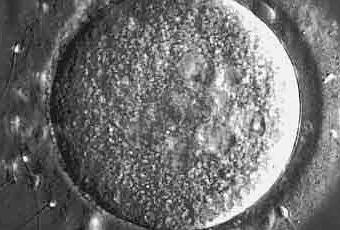

Figura IMG-01. El óvulo posee una serie de estructuras asociadas que lo protegen y que sirven como agentes de selección sexual, a su alrededor de encuentra una matriz de proteína llamada zona pellucida y una capa de células granulosas/foliculares.